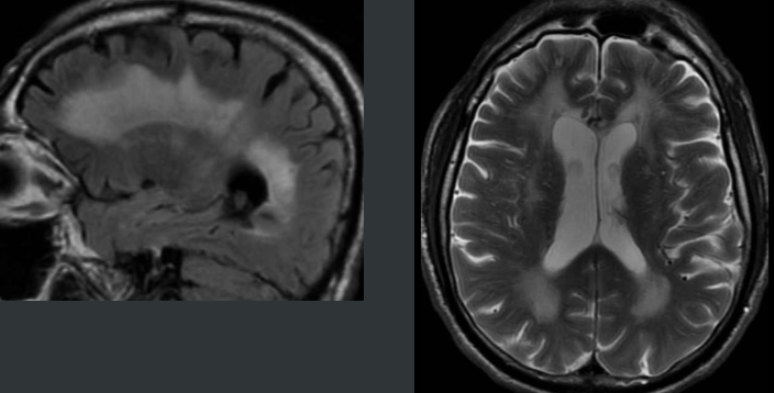

Lecoencéphalopathie Multifocale Progressive (LEMP / PML)

- JC Virus (réactivation)

- Patients immunodéprimés ++ (HIV, transplantés)

- SEP sous Tysabri (Natalizumab) = Rares

- Démyélinisation asymétrique avec atteinte des fibres en U

- Les lesions partent des fibres en U et s’étendent en profondeur

- La prise de contraste est en périphérie (front actif)

- Pas d’effet de masse (pas un processus infiltratif)

- Diagnostic final PCR voir biopsie cérébrale

- Mauvais pronostic (péjoration progressive → décès)

- Le Front infllammatoire peut se “reveiller” quand le patient regagne une immunité et mimer une progression alors que c’est la réponse immunitaire = IRIS (Immune reconstitution inflammatory syndrome)